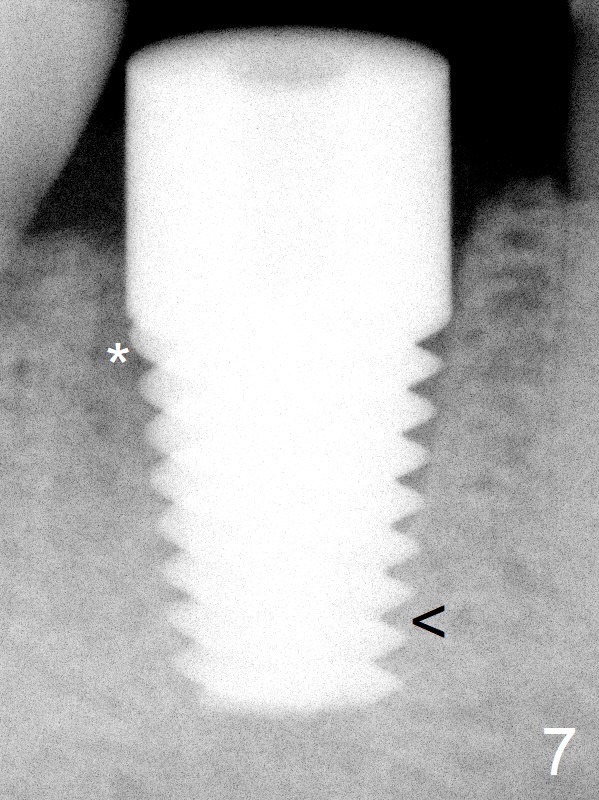

Fig.7: When 7x17 mm implant is placed with > 60 Ncm, the mesial socket is obliterated while the density of the distal one increases because of autogenous bone grafting (*). The apical threads of the implant have engaged into the mesial wall of the socket for primary stability (<).